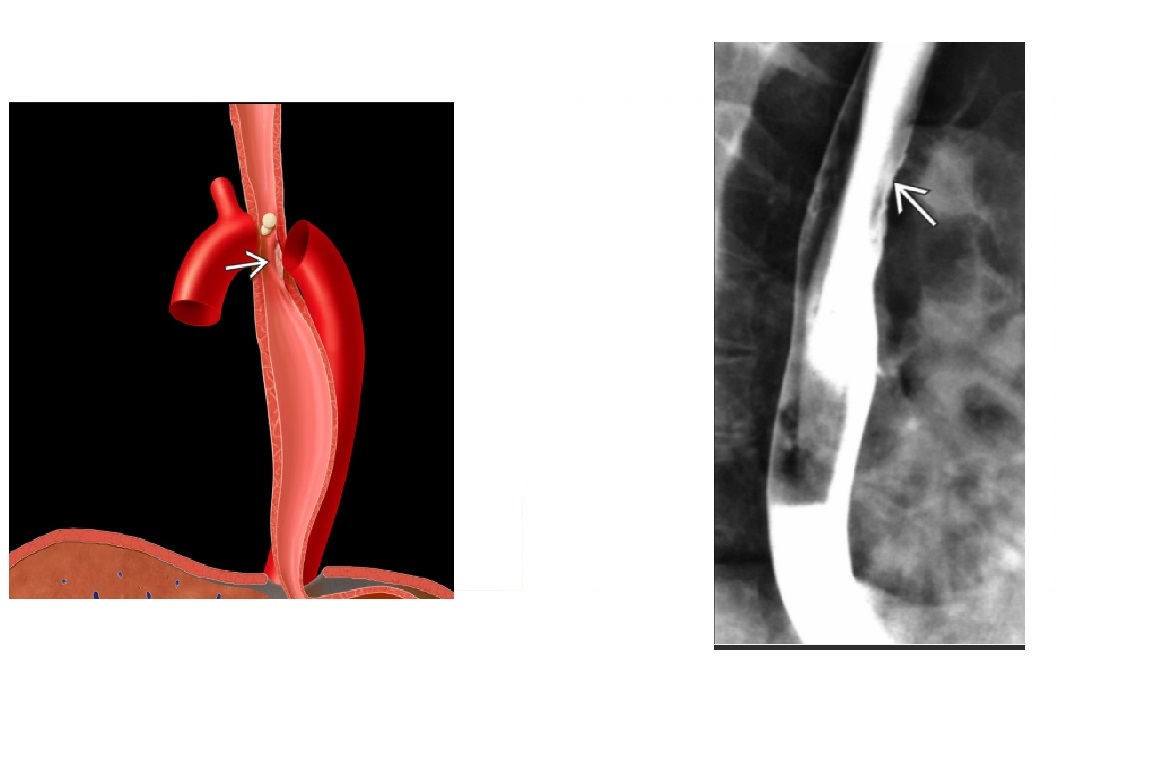

-affects the Lower 2/3 (smooth muscle) with atony and peristalsis that begin caudally and moves cranially.

-Moderate dilatation of esophagus with fusiform stricture at lower end

Achalsia

- Grossly dilated whole oesophagus with smooth, beak-like tapering at lower end

Reflux Esophagitis (With Stricture)

-Longer tapered distal stricture

-Less luminal dilation

-Distinguished from scleroderma by normal peristalsis

Esophageal Carcinoma

-Abrupt proximal borders of strictured segment (rat tail appearance)

-Mucosal irregularity, shouldering, mass effect